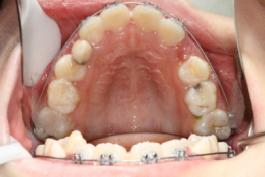

❸ 牙齿不齐:影响咬合关系,影响美观。

前

后